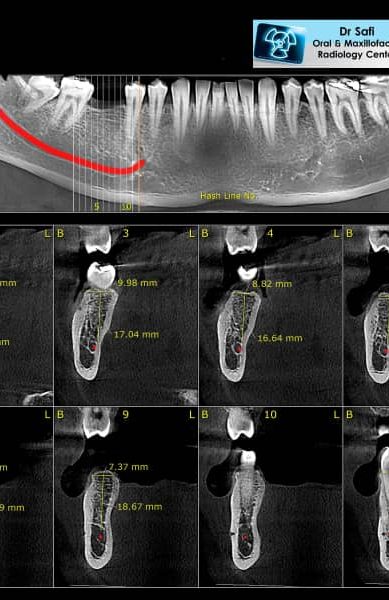

Dr. Yaser Safi's Center for Oral and Maxillofacial Radiology